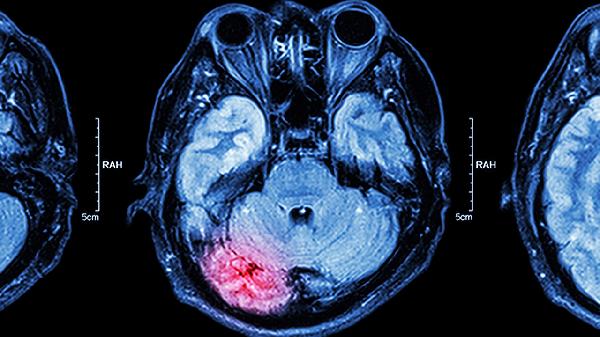

做头颅CT检查能确诊脑癌吗

头颅CT检查通常不能直接确诊脑癌,但可作为初步筛查手段。脑癌的确诊需要结合病理活检、核磁共振成像、肿瘤标志物检测、临床症状评估以及多学科会诊等综合判断。 头颅CT能清晰显示脑部结构异常,如占位性病变